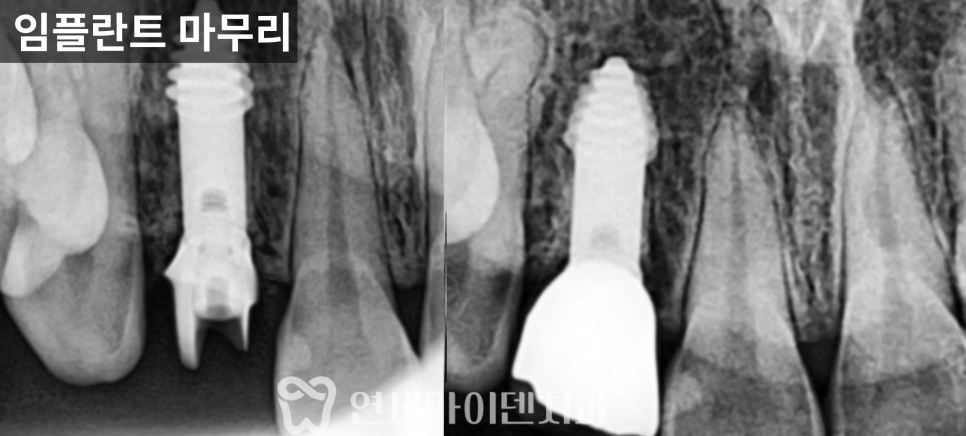

최종 보철과 주변 치아 관리

약 3개월의 치유 기간 후

임플란트 보철을 완성했고,

해당 부위로 다시

안정적인 저작이 가능한 상태가 되었습니다.

또한 인접 치아의 신경치료 상태가

완전하지 않은 부분이 확인되어

추후 문제가 생기지 않도록

함께 정리하는 치료를 진행했습니다.